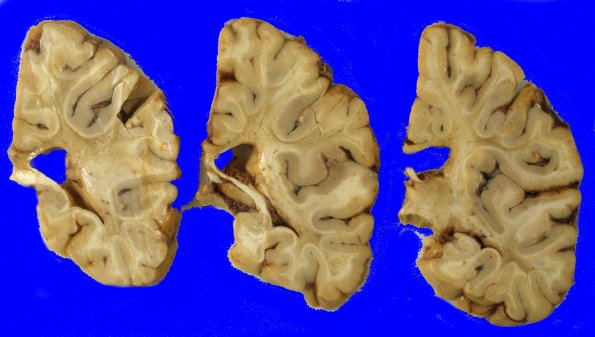

Subcortical Arteriosclerotic Encephalopathy

3A4 Binswanger's Dz (Case 3) 7

More caudally the white matter discoloration is more patchy.